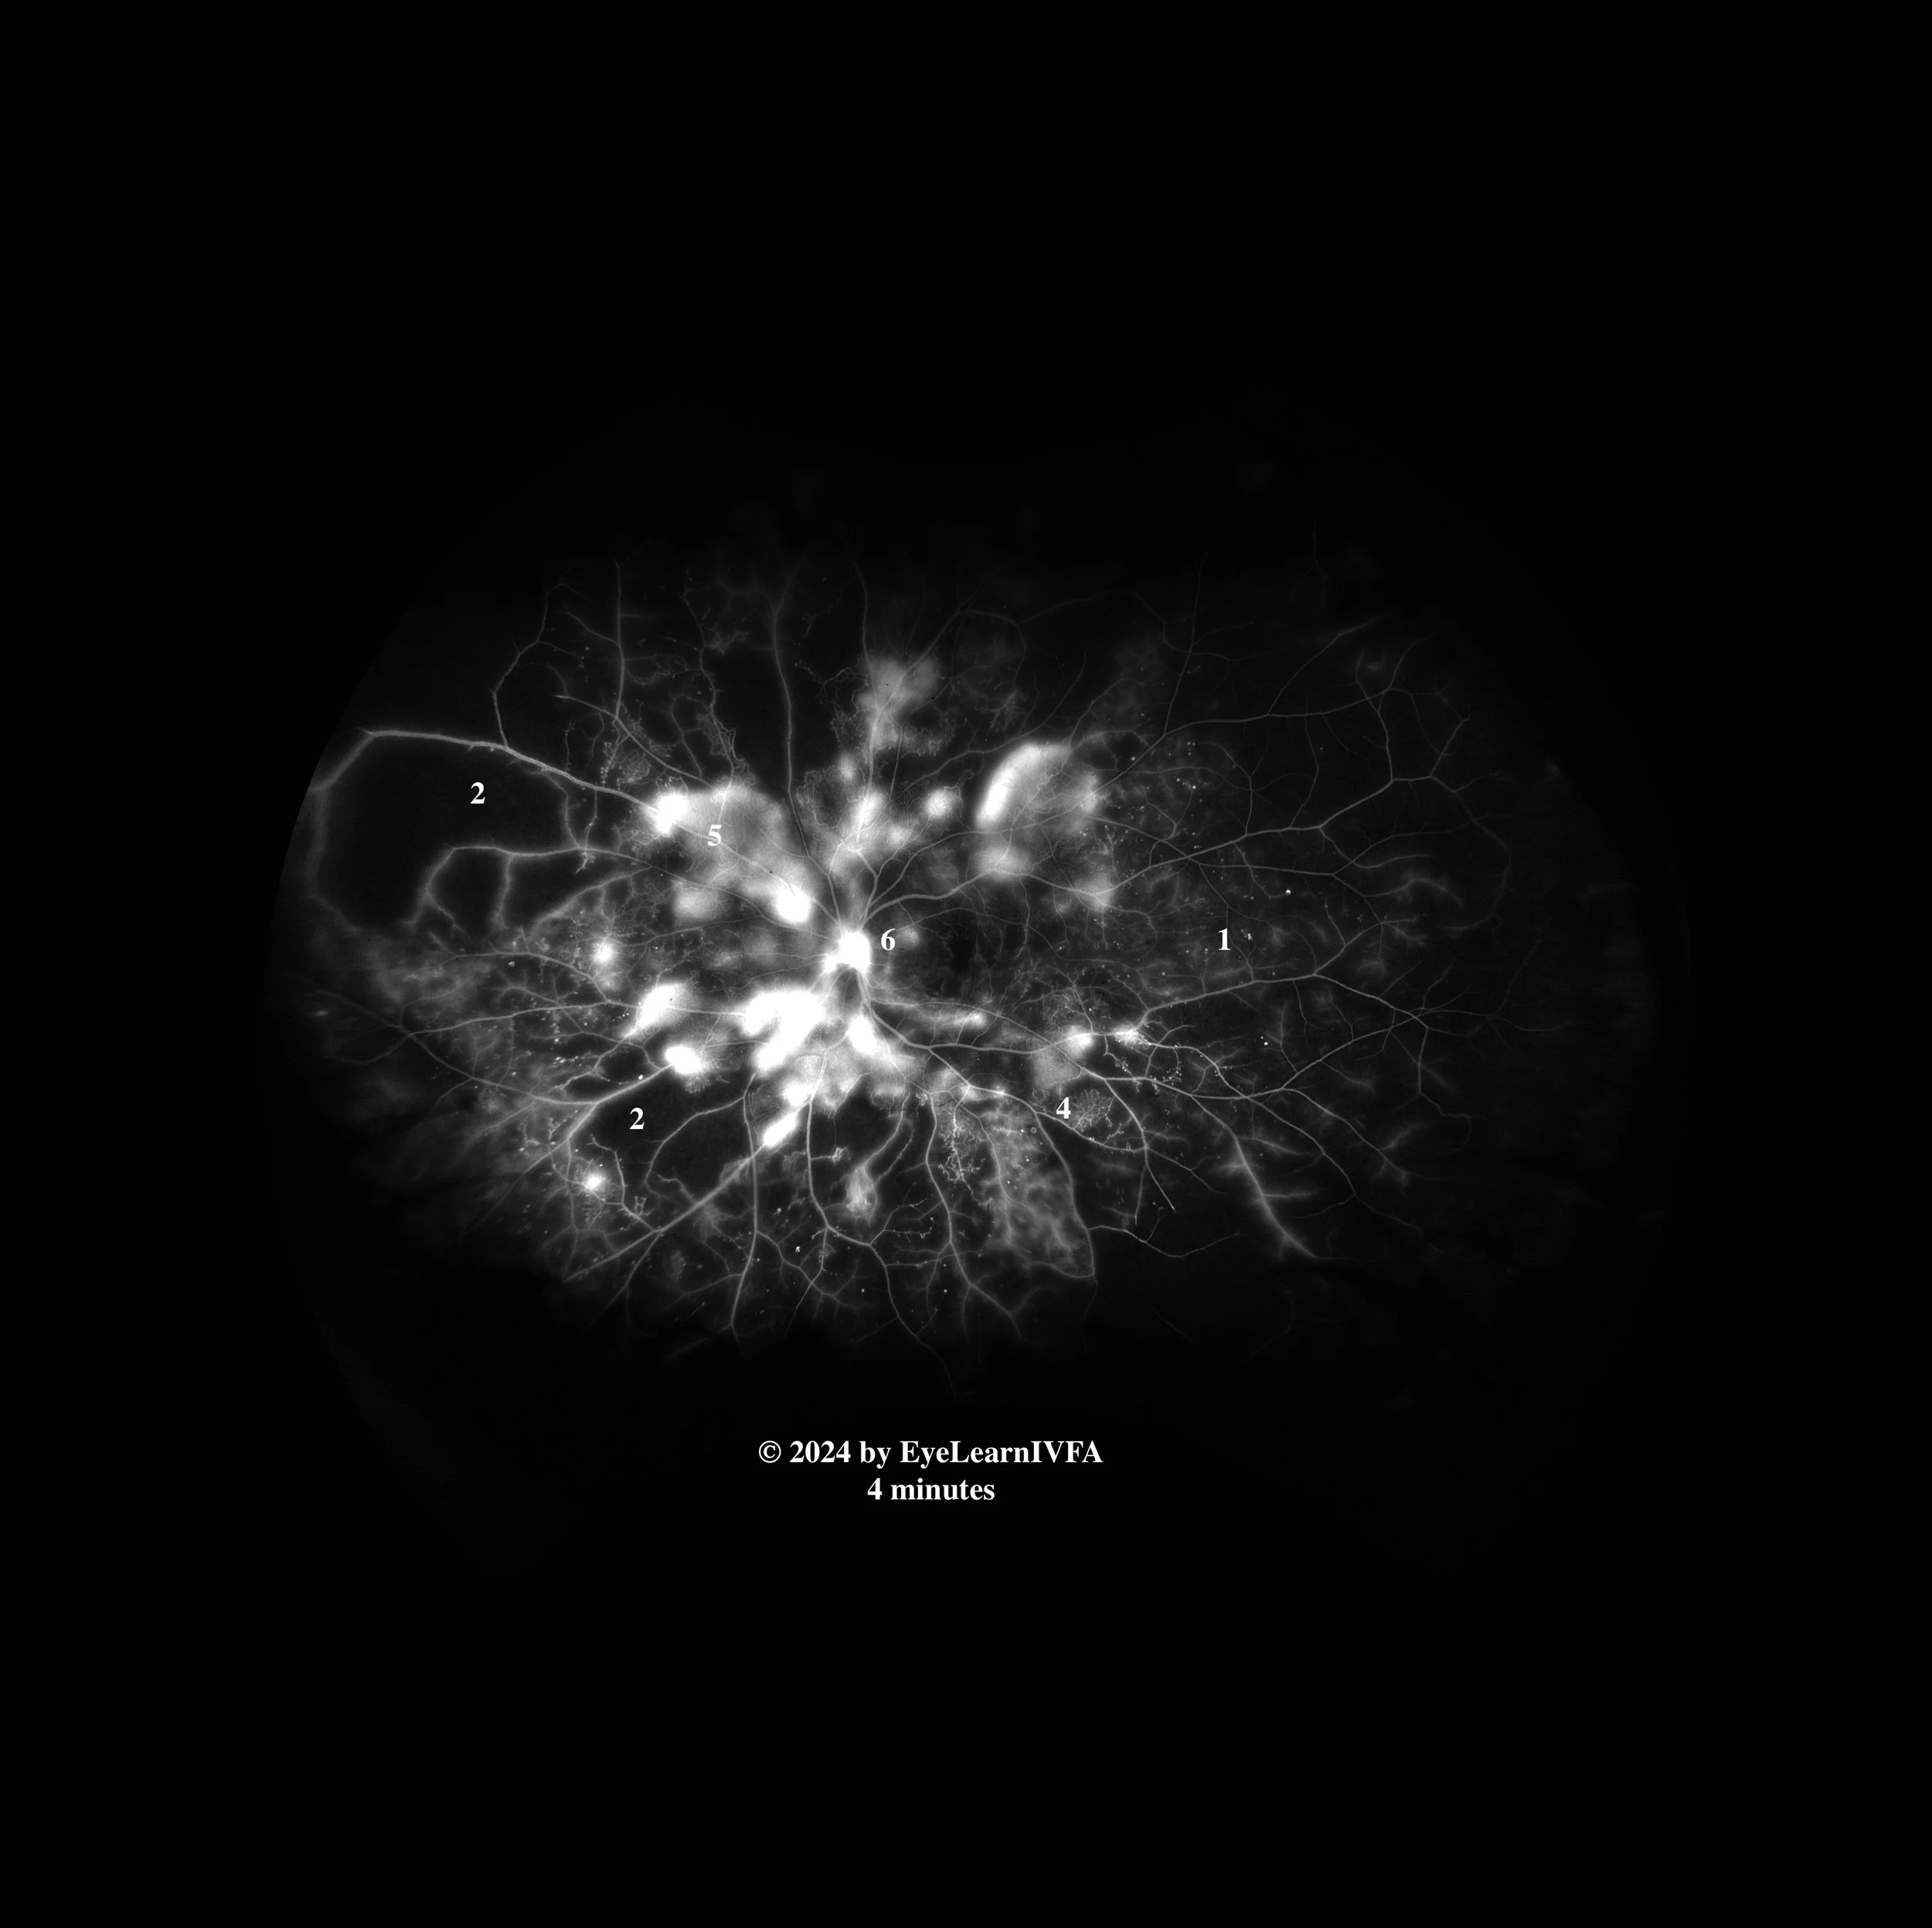

Retina Case #1